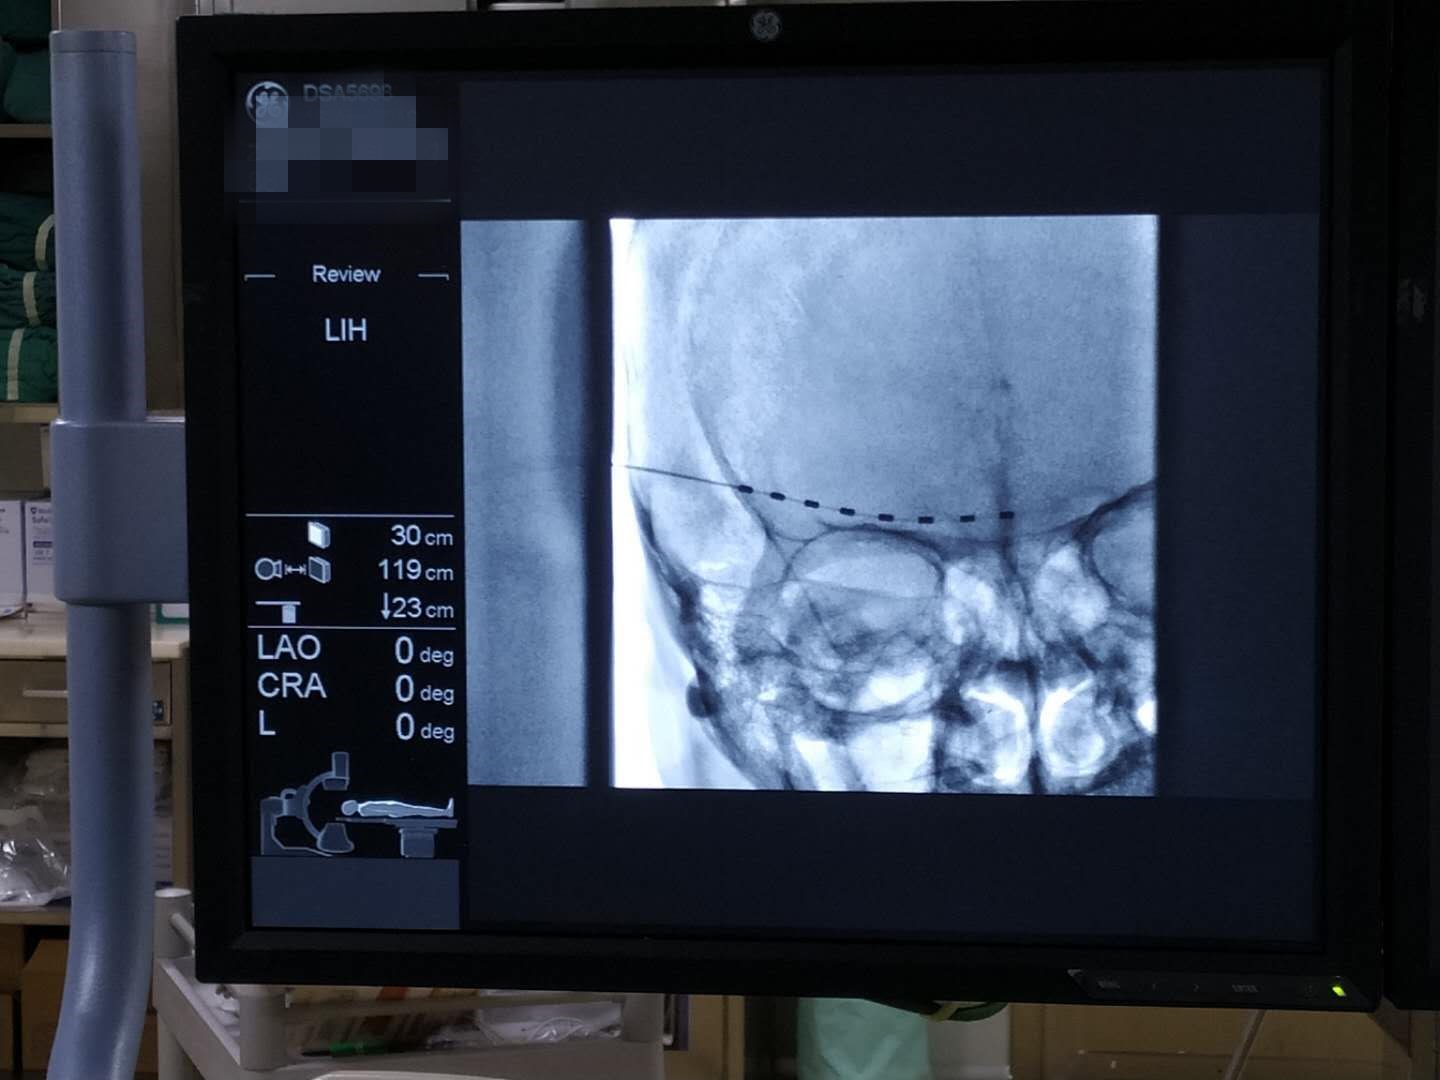

经过了充分准备与耐心沟通,曹启旺主任及团队为张嗲在开展了眶上神经刺激电极植入术,经过9天的持续电刺激治疗后拔除刺激电极,张嗲的疼痛完全缓解、右眼流泪畏光症状消失、视力明显恢复。出院时张嗲嗲感慨道:“早知道我应该一开始就到省人民医院疼痛科来看了,就不用受这么多的罪。”